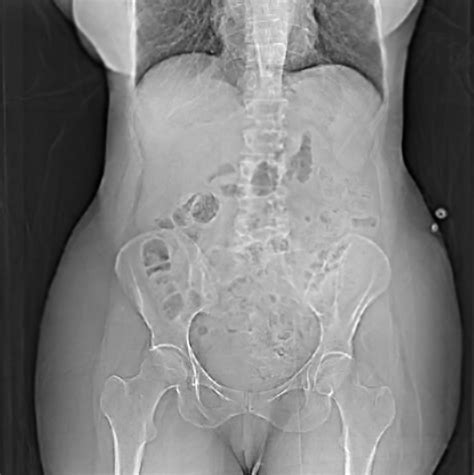

Pelvic Prolapse After Hysterectomy

Pelvic Prolapse After Hysterectomy